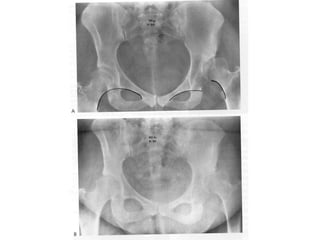

Direkt Radyografi Bulguları

• Epifiz çekirdeklerinin gözükmediği

dönemdeki bulgular erken radyografik

bulgulardır.

• Epifiz çekirdekleri ilk 5-6 ay ossifiye

olmadıkları için gözükmezler.

• Epifiz çekirdekleri gözükmeye başladığı

dönemdeki bulgular geç radyografik

Asetabular açı

• Her iki Y kıkırdağını birleştiren Hilgenreiner çizgisi

• Bu çizgiye asetabulumun üst dış kenarı ile Y

kıkırdağı arasındaki ikinci çizgi

• İki doğru arasındaki açıya asetabular açı denir.

• Yenidoğanda bu açı ortalama 27.5 derecedir. 30

derecenin üzeri patolojiktir ve asetabular

displaziyi gösterir

Shenton-Menard Hattı

• Ön-arka, nötral pelvis grafisinde femur

boynunun medial kenarı ile obturator

foramenin üst kenarı birbirini izleyen bir ark,

bir yay oluştururlar. Bu hatta Shenton-Menard

Hattı denir. GKD’ de bu hat, bu yay kırılır

Perkins kadranları

• Hilgenreiner çizgisine asetabulumun üst

kenarından bir dik çizgi çizilir. Alt-iç, alt-dış,

üst-dış ve üst-iç olmak üzere dört kadran

ortaya çıkar. Femur başı epifizinin normalde

alt-iç kadranda olması gerekir. Eğer alt-dış

kadranda gözüküyorsa sublukse kalça, üst-dış

kadranda ise disloke kalça denir

Radiological Diagnosis

• classic features

– increased acetabular index ( n=27, >30-35 dysplasia)

– disruption shenton line ( after age 3-4 should be intact on all

views)

– absent tear drop sign

– delayed appearance ossific nucleus and decreased femoral

head coverage

– failure medial metaphyseal beak of proximal femur

, secondary ossification center to be located in lower inner

quadrant

– center-edge angle useful after age 5 ( < 20) when can see

ossific nucleus

X-ray

Putti Triadı:

Asetabuler displazi,

Hipoplazik femur başı,

Üst-dış yerleşimli femur başı.